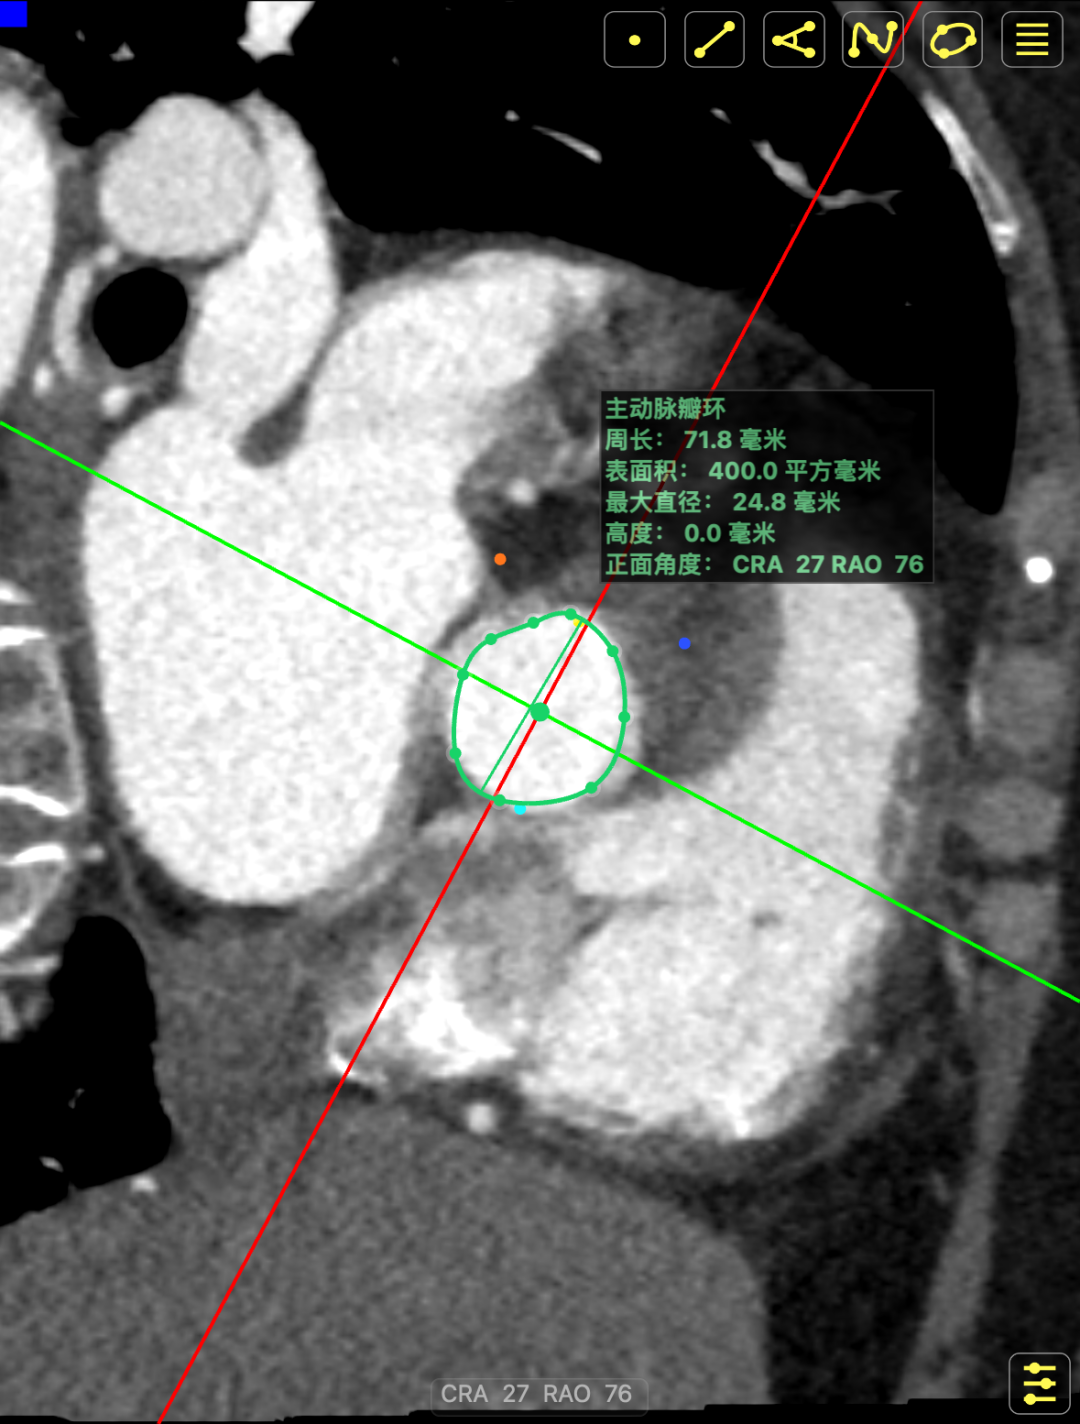

术前CT提示

主动脉瓣多发钙化,主动脉瓣为type0型二叶瓣中重度钙化。主动脉瓣环面积折算直径约24mm。患者双侧冠脉开口高度可(左冠14.46mm,右冠18.29mm),主动脉升弓降部管壁不规则并钙化斑块影,主动脉弓并龛影。升主动脉管径36mm,降主动脉管径22mm。腹主动脉、双侧髂动脉管壁不规则并可见钙化斑块影,双侧髂总动脉及其分支髂内动脉管腔轻度狭窄。

CT影像